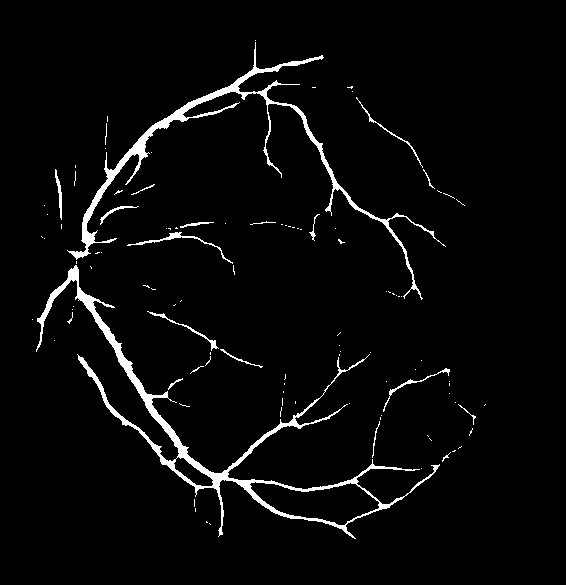

Figure 8: Visual results for two sample STARE images.

Cross Validation

Cross-validation is used to assess the performance of the proposed model on ten images from the STARE dataset. STARE images are more challenging due to the inherent lower quality and poor contrast of these images. However, the proposed model achieves reasonable performance on the STARE dataset images. Typically, training is conducted on STARE images using leave-one-out validation to test the model’s validity. Very few works have provided cross-validation to evaluate the stability of the learned model on the STARE dataset. The average values 88.06/96.31 for Se/Sp are quite promising and demonstrate the significant performance of the proposed model. The average AUC value is 97.57% that reflects the generalization of the proposed model on a completely unseen STARE dataset to demonstrate its generalization capability. Therefore, we, believe that our proposed methodology can be reliably applied for automatic retinal vessel segmentation of the clinical applications, such as a computer-aided diagnosis pipeline or automated vascular quantification or localization. Figure 8 depicts the visual outcomes for 2 sample images from the STARE dataset. As evident from a visual comparison of ground truth and output segmentation masks, thick vessels are detected quite accurately, especially near the fovea region. Similarly, thin vessel pixels at the branches are also segmented with reasonable visual match.